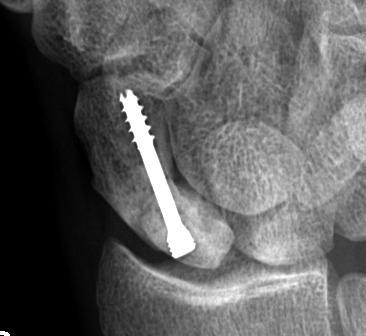

< 60 with good bone stock and preserved joint space

Union rates increased with anatomical reduction

Options

- closed reduction

- open reduction / if closed reduction fails